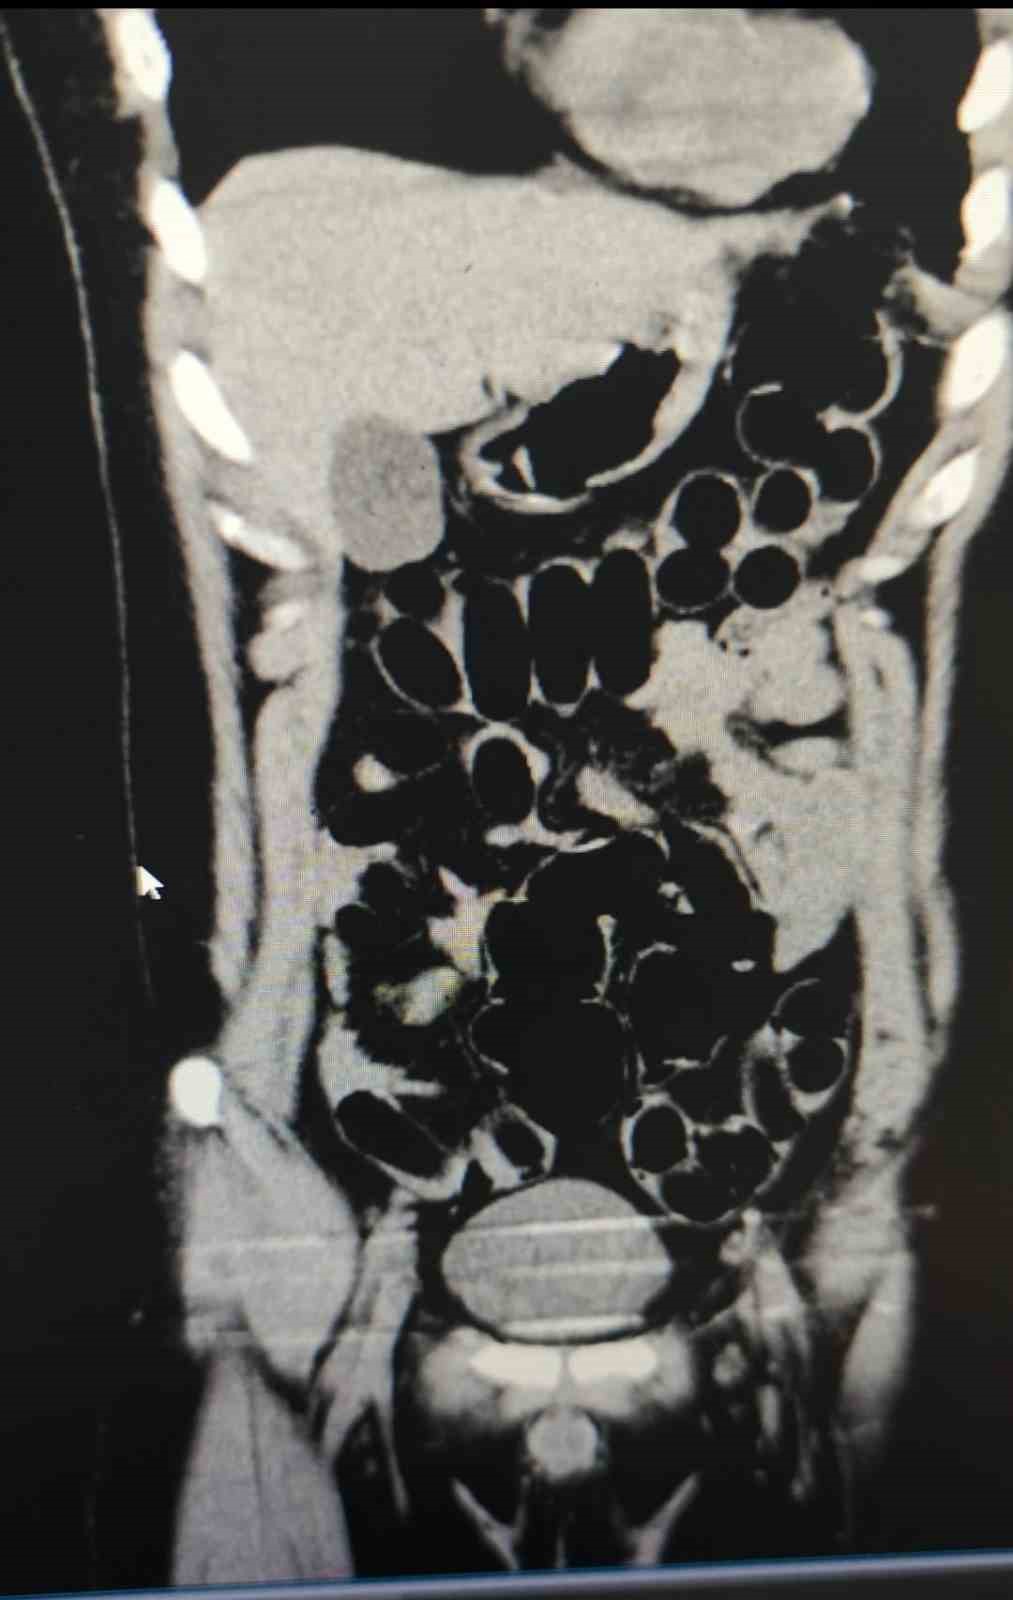

Muş Valiliğinden yapılan yazılı açıklamada, "Muş İl Emniyet Müdürlüğü Narkotik Suçlarla Mücadele Şube Müdürlüğümüz ekiplerince, ilimiz ve Batı illerine yönelik uyuşturucu madde sevkiyatının önlenmesine yönelik yürütülen risk analizi çalışmaları sonucunda, bir şüphelinin uyuşturucu madde taşıdığı değerlendirilmiştir. 25 Aralık 2024 tarihinde saat 02.20’de, şüphelinin bulunduğu şehirlerarası yolcu otobüsü, ekiplerimizce il merkezine girişte oluşturulan kontrol noktasında durdurulmuştur. Otobüste yolcu olarak bulunan S.S. isimli şahıs, görevlilerimizin sorgulaması sonucunda şüpheli görülerek hastaneye sevk edilmiştir. Hastanede yapılan iç beden muayenesi ve tomografi görüntüleri sonucunda, şahsın midesinde uyuşturucu madde taşıdığı tespit edilmiştir. Hastanede yapılan tespit sonrasında şüpheli şahsın midesinden toplam 84 adet kapsül içerisinde daralı ağırlıkları 842 gr gelen eroin maddesi ele geçirilmiştir. Şüpheli şahıs, ’Uyuşturucu ve Uyarıcı Madde Ticareti’ suçundan gözaltına alınmış, işlemlerinin ardından adli makamlara sevk edilmiş ve tutuklanmıştır. Uyuşturucu ile mücadelemiz kararlılıkla devam etmektedir” denildi.